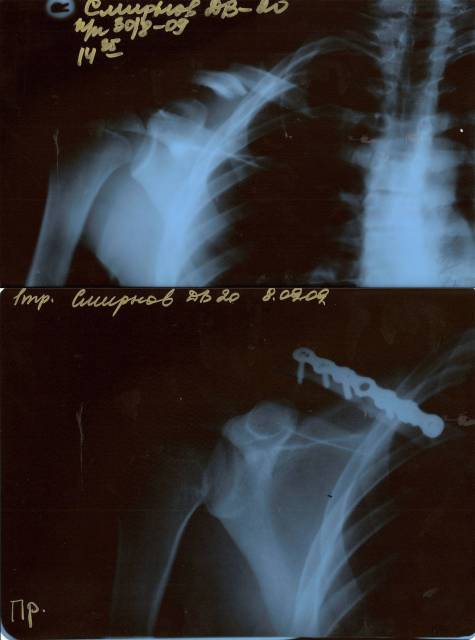

Главная > Железки > Поломки и падения

Ключицоломательный год видимо)

Кроме меня ещё двух знаю)

Никому не пожелаю)

чёто она както с пластиной тоже не на месте. выздоровливай. сам этим летом заработал винт в запястье на всё жизнь

спасибо. пункт назначения 4 смотрел. с пластиной там норм все.

такое чувство будто тебе цепью скрепили.. поправляйся

adekcandr [Сент 13, 2009 в 10:53 ]

Цепи опасны!!!Вон,гадина,как к ключице присосалась!!!ОПАСНОСТЕ!!!!

Squibble [Сент 13, 2009 в 11:35 ]

Да это есть цепь) KHC с байка снял им дал)

Один в один как у меня)))) Выздоравливай) Когда вынимать будут проси чтобы на памят оставили - крутая штучка)

Squibble [Сент 13, 2009 в 12:45 ]

норм, у меня прям в том же месте так же было. и тоже на 5 болтов крепили. пластину потом на вынос прикрепить можно)))) у меня на выносе. а так поправляйся и не унывай - я через месяц катал уже, даже раньше. по лайту недели через 3 после операции начал

Да, в этом году много людей ключицу поломало. Я умудрился аж два раза сломать одну и тужу, притом второй раз вместе с пластиной сломал =)